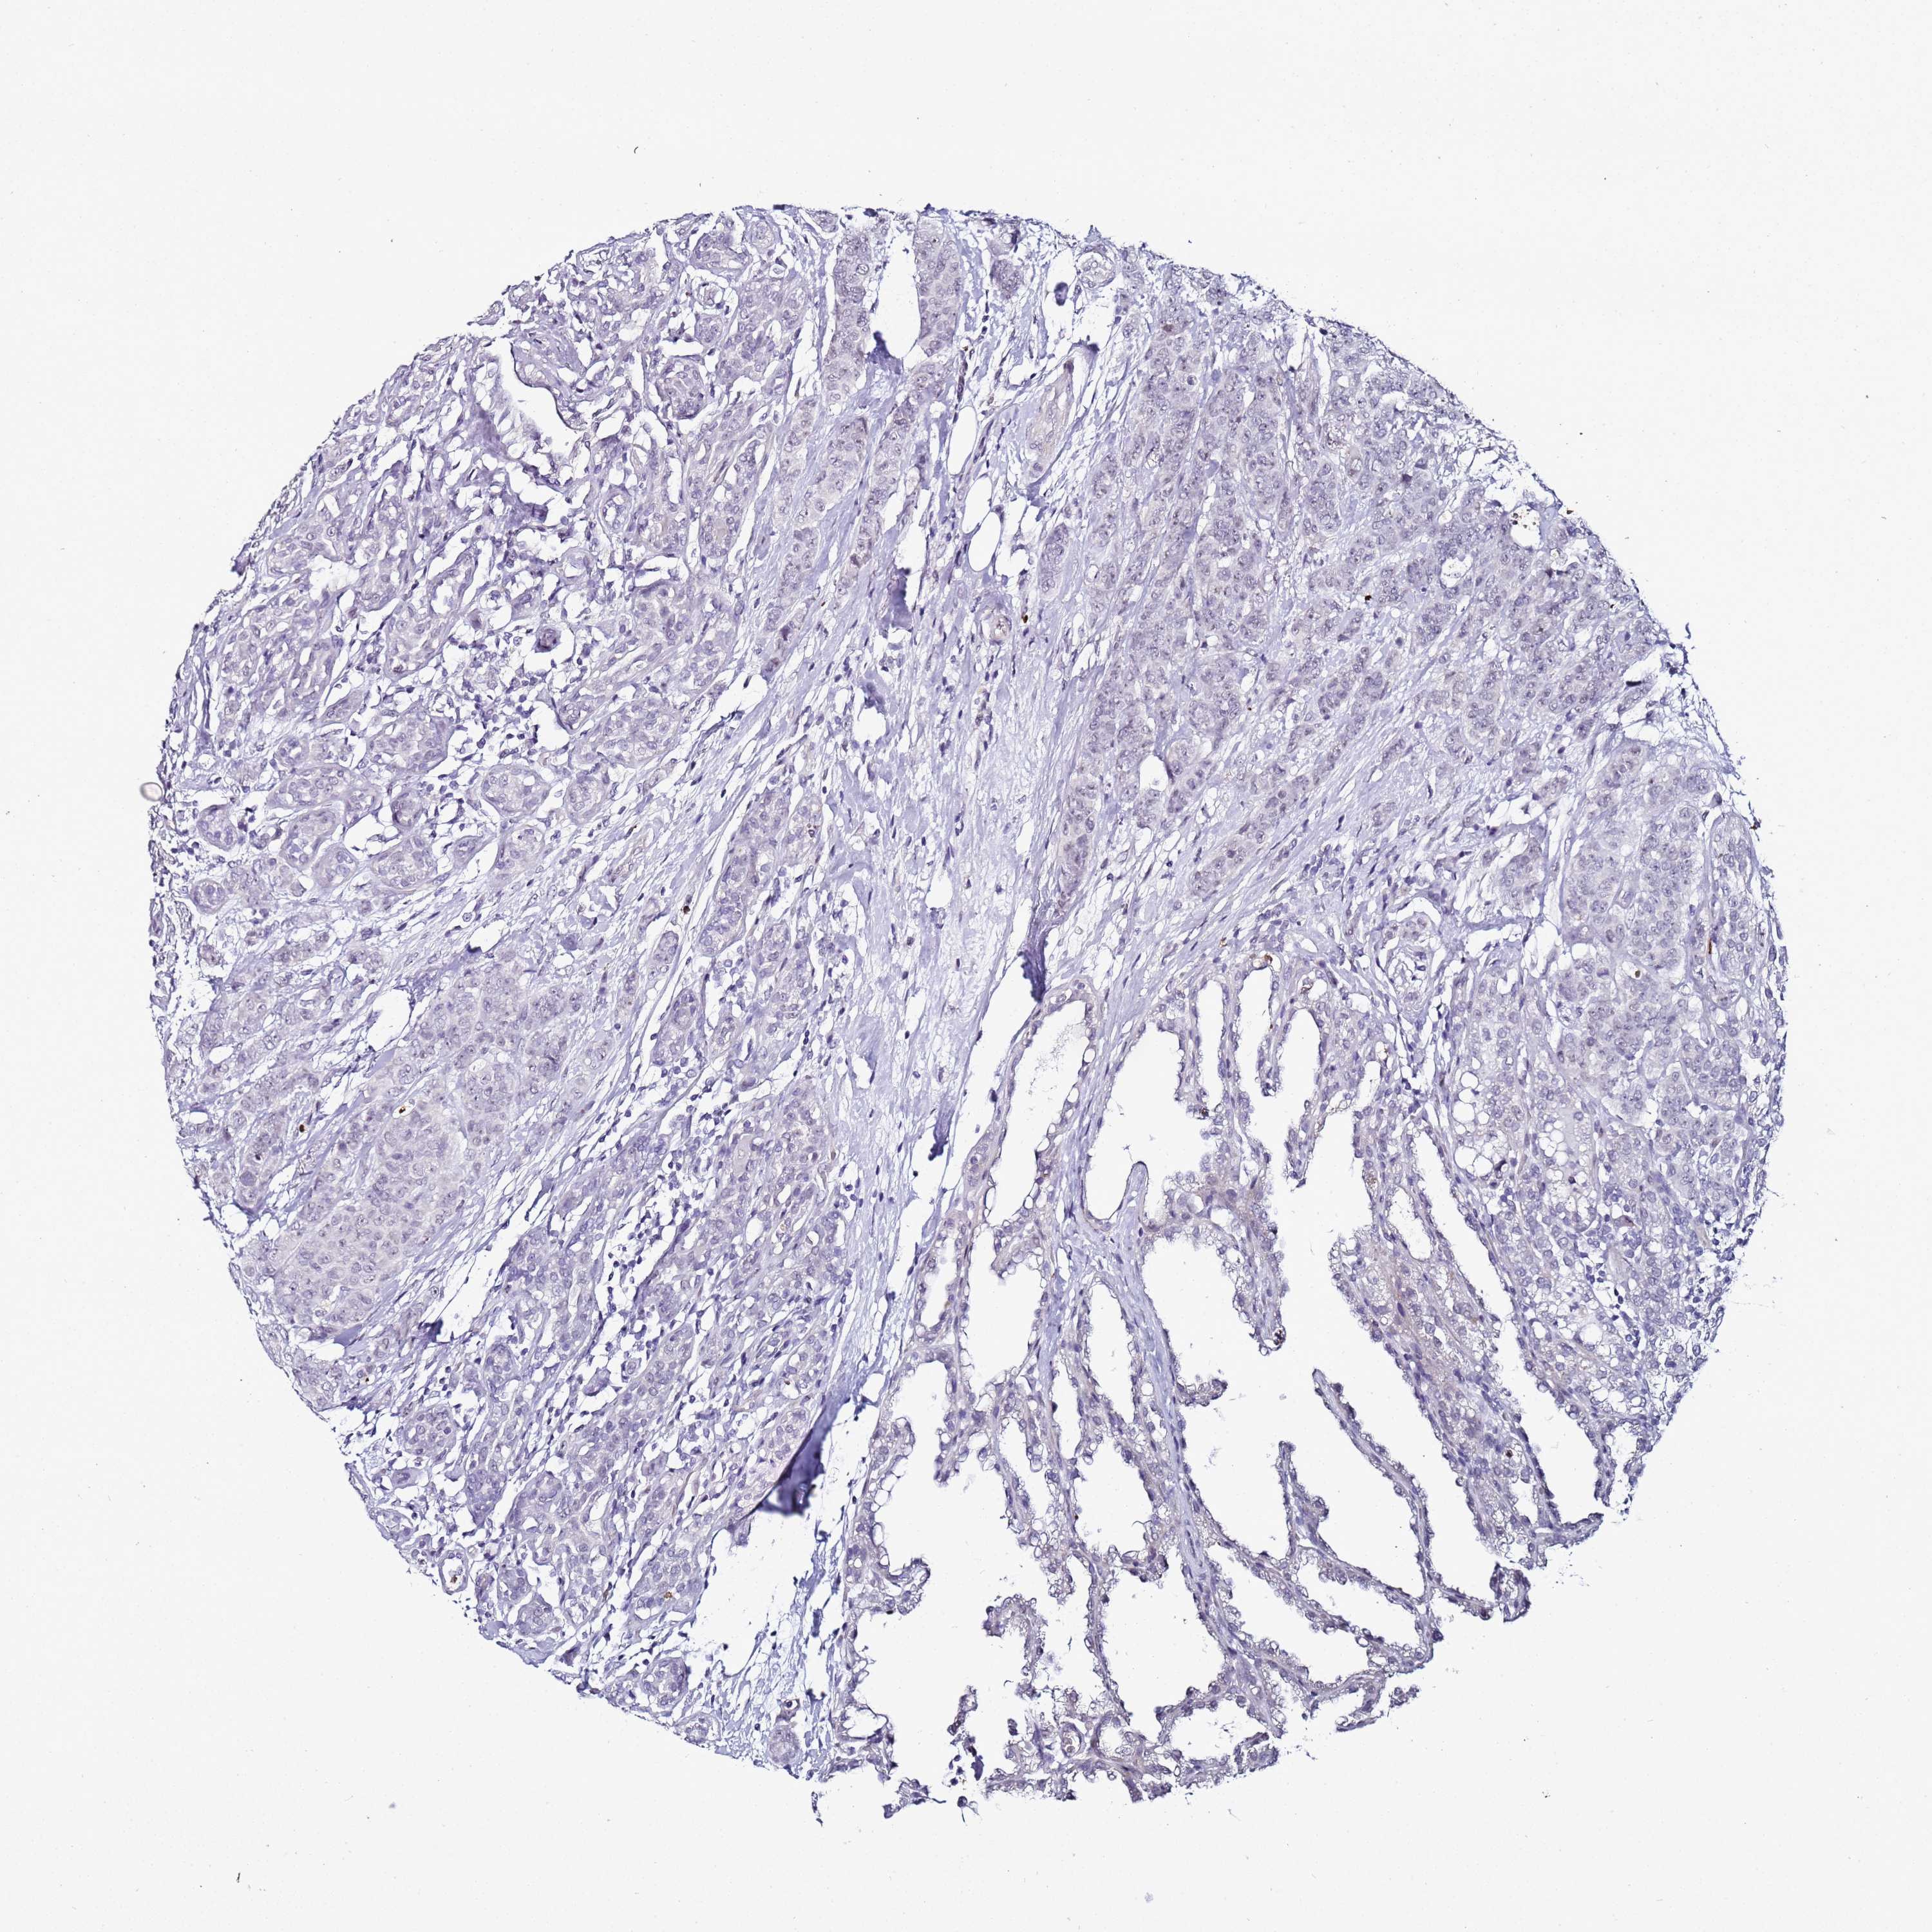

CANCER BREAST CANCER Show tissue menu

BRCA TCGA BRCA VALIDATION PROTEIN EXPRESSION

ANTIBODIES

AND

VALIDATION